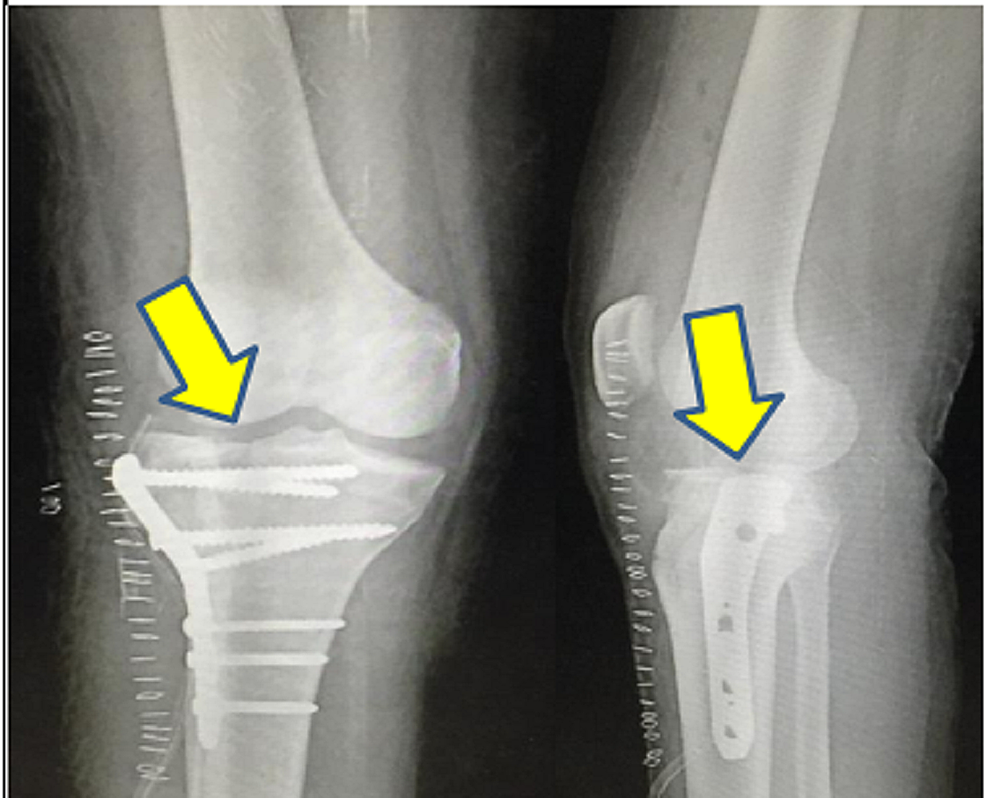

Post-operatively, the patient received intravenous amoxicillin-potassium clavulanate 1.2 g twice daily for seven days and amikacin sulfate 500 mg twice daily for five days followed by oral amoxicillin-potassium clavulanate 625 mg twice daily for seven days. Post-operative radiograph of the operated knee joint was taken on post-operative day 2, as shown in Figure 3. An above-knee slab support was applied, and the patient was advised strict non-weight bearing for six weeks. Culture and sensitivity from surgical site showed staphylococcus epidermidis, which was sensitive to tetracycline and doxycycline. The patient was started on tablet doxycycline 100 mg twice a day for 14 days. All staples were removed on post-operative day 14, and the surgical site was found to be healthy. The patient underwent physiotherapy in the form of muscle stimulation test 15 minutes daily till he recovered from the foot drop. The guarded continuous passive motion was also started for the patient. At discharge, range of motion at the knee joint was 0- to 120-degree flexion after one month of physiotherapy. Tinel sign was positive 1-cm along the common peroneal nerve distribution at the level of the middle third of the leg. The patient had recovered from the foot drop (possibly due to neuropraxia). Partial weight bearing was initiated after six weeks. The patient was allowed full weight bearing at three months. At the last follow-up, six months post-injury, he was walking without any difficulty.